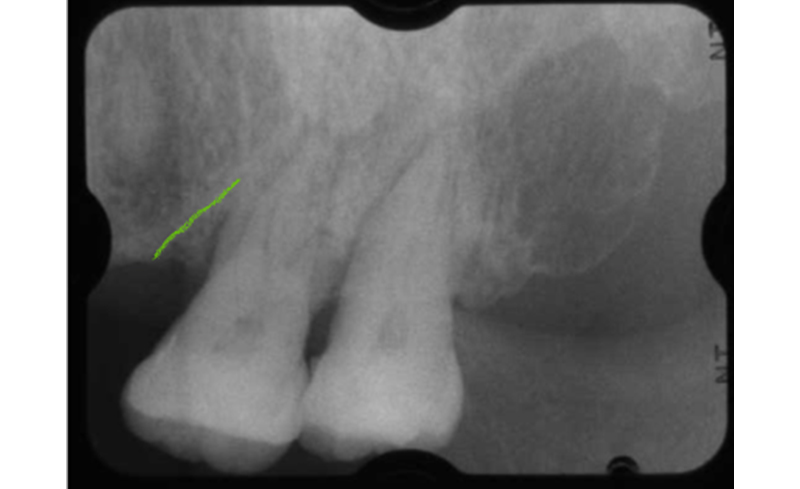

上の二枚は初診時。大きな歯石(赤マル)が大量に歯根面に沈着し、それに伴い骨の吸収が認められます(青矢印)。下の二枚が5年後。骨の吸収が止まり一部骨再生が認められます(緑矢印)。

| 年齢 | 48歳男性 |

|---|---|

| 治療内容 | 初診時に左上の大臼歯部に骨の吸収が認められます(左図)。再生療法を行い点線部が領域が再生されました(右図)。 |

| 治療内容 | 初診時に左上の大臼歯部に骨の吸収が認められます(左図)。いちばん後ろの歯は破折のため抜歯しました。手前の歯に再生療法を行い点線部が領域が再生されました(右図)。 |